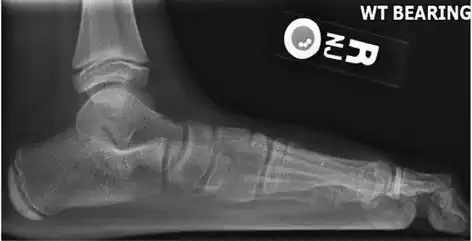

On plain radiography, flat feet can be diagnosed and graded by several measures, the most important in adults being the talonavicular coverage angle, the calcaneal pitch, and the talar-1st metatarsal angle (Meary's angle).[11] The talonavicular coverage angle is abnormally laterally rotated in flat feet.[11] It is normally up to 7 degrees laterally rotated, so a greater rotation indicates flat feet.[11] Radiographies generally need to be taken on weightbearing feet in order to detect misalignment.[12]